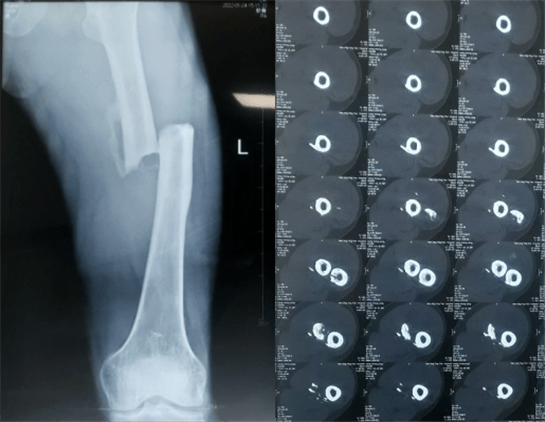

患者:男性,43歲,左股骨干骨折髓內(nèi)釘內(nèi)固定術(shù)

醫(yī)院:南京應(yīng)天骨科醫(yī)院

股骨是下肢的主要負(fù)重骨,有其特殊的解剖關(guān)系,周圍肌肉發(fā)達(dá),因此一旦股骨干骨折后如果治療不當(dāng),容易造成肌肉牽拉,導(dǎo)致畸形和功能障礙。治療股骨干骨折,必須遵循恢復(fù)肢體的長度及力線,無旋轉(zhuǎn),盡量行以微創(chuàng),保護(hù)骨折局部血運(yùn),促進(jìn)愈合。髓內(nèi)釘對(duì)骨折的固定能夠達(dá)到較大的穩(wěn)定性和堅(jiān)固性,可以減少醫(yī)源性污染,減少軟組織分離及周圍血供破壞,有利于骨折早期愈合,是治療股骨干骨折的首要治療方法。

術(shù)前檢查

大平板一體式C形臂術(shù)前檢查